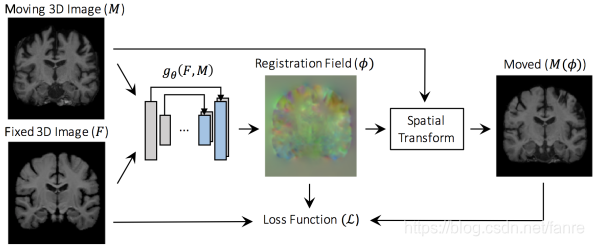

图2.2 整体的模型图,voxelmorph学习一个变换 来事的moving image

来事的moving image 形变后与fixed image

形变后与fixed image 对齐,损失函数就是度量warped image

对齐,损失函数就是度量warped image 和fixed image

和fixed image 之间的相似性,并同时约束变换

之间的相似性,并同时约束变换 的光滑性。

的光滑性。

voxelMorph最小化的cost function:

F和M就是两幅输入的图像, 是一个形变场,

是一个形变场, 是用来度量

是用来度量

之间的相似性,

之间的相似性, 是deformation field 的正则项

是deformation field 的正则项 是正则项权重。

是正则项权重。 可以使mean squared error 或者是cross-correlation。

可以使mean squared error 或者是cross-correlation。